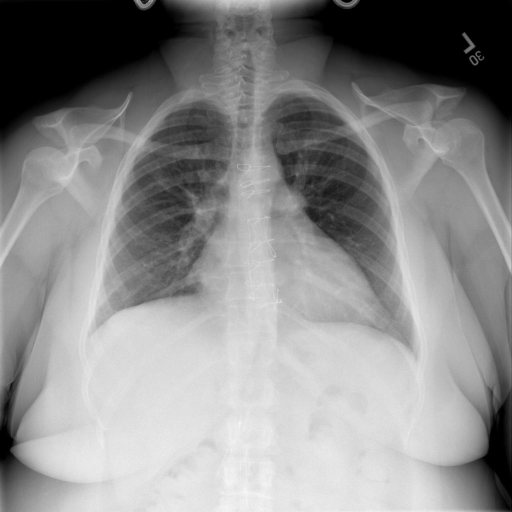

# 本文贡献 ![](./assets/images/xrayglm.png) - 借助ChatGPT以及公开的数据集,我们构造了一个`X光影像-诊断报告`对的医学多模态数据集; # 数据集 - [MIMIC-CXR](https://physionet.org/content/mimic-cxr-jpg/2.0.0/)是一个公开可用的胸部X光片数据集,包括377,110张图像和227,827个相关报告。 - [OpenI](https://openi.nlm.nih.gov/faq#collection)是一个来自印第安纳大学医院的胸部X光片数据集,包括6,459张图像和3,955个报告。 在上述工作中,报告信息都为非结构化的,不利于科学研究。为了生成合理的医学报告,我们对两个数据集进行了预处理,并最终得到了可以用于训练的**英文报告**。除此之外,为了更好的支持中文社区发展,借助ChatGPT的能力,我们将英文报告进行了中文翻译,并最终形成了可用于训练的数据集。 |数据集|数量|下载链接| |:-|:-|:-| |MIMIC-CXR-zh|-|-| |OpenI-zh|6,423|[诊疗报告](./data/Xray/openi-zh.json) 、[X光影像](https://pan.baidu.com/s/13GBsDMKf6xBZBSHpoWH_EA?pwd=k9sh)| # 快速上手 1. 安装环境 ```bash # 安装依赖 pip install -r requirements.txt # 国内换源安装依赖 pip install -i https://mirrors.aliyun.com/pypi/simple/ -r requirements.txt ``` 此时默认会安装`deepspeed`库(支持`sat`库训练),此库对于模型推理并非必要,同时部分`Windows`环境安装此库时会遇到问题。 如果想绕过`deepspeed`安装,我们可以将命令改为: ```bash # 安装依赖 pip install -i https://mirrors.aliyun.com/pypi/simple/ -r requirements_wo_ds.txt # 安装SwissArmyTransformer pip install -i https://mirrors.aliyun.com/pypi/simple/ --no-deps "SwissArmyTransformer>=0.3.6" ``` 2. 模型推理 CLI推理: ```python python cli_demo.py --from_pretrained checkpoints/finetune-XrayGLM-05-25-01-04 --prompt_zh '详细描述这张X光影像' ``` 更多[参数](https://github.com/WangRongsheng/XrayGLM/blob/main/cli_demo.py#L16) # 效果展示 |X光影像|诊疗报告(医生)|XrayGLM| |:-|:-|:-| |![](./data/Xray/2_1.png)|根据X射线图像,心脏大小正常,肺部看起来很清晰。已经排除了肺炎、积液、水肿、气胸、腺病、结节或肿块的存在。该发现表明一切正常。换句话说,总体印象是胸部正常。|X光片显示,心脏大小正常。肺部没有气胸或胸腔积液的证据。骨骼结构看起来没有任何异常。总的来说,X光片表明没有发现急性心肺疾病的迹象。| |![](./data/Xray/2882_1.png)|X光图片显示没有扭曲的区域、可疑的骨质不透明度或胸腺积液。心脏大小轻微增大,但非常稳定。此外,没有气胸的证据,肺野也正常。总体来说,X光片显示没有急性心脏异常,但要注意轻微的心脏扩大。|X光片显示,心脏大小正常。肺部和纵隔轮廓清晰,没有气胸或胸腔积液的证据。骨骼结构完整,没有任何急性异常。| |![](./data/Xray/2577_1.png)|心影形态在正常范围内。没有急性骨质异常。有可能出现没有明显的吸水或肺实质状况的线索。没有大面积积液或气胸。有可能怀疑其有误吸或肺实质问题。为了确诊和治疗,可能需要进行适当的影像学随访。|心脏大小正常,肺部和纵隔轮廓清晰。没有急性异常或活动受限的证据。没有任何明显的气胸、胸腔积液或肺不张的迹象。此外,也没有发现任何局灶性骨质异常或其他急性疾病。| # 项目致谢 1. [VisualGLM-6B](https://github.com/THUDM/VisualGLM-6B)为我们提供了基础的代码参考和实现; 2. [MiniGPT-4](https://github.com/Vision-CAIR/MiniGPT-4)为我们这个项目提供了研发思路; 3. ChatGPT生成了高质量的中文版X光检查报告以支持XrayGLM训练; 4. [gpt_academic](https://github.com/binary-husky/gpt_academic)为文档翻译提供了多线程加速; 5. [MedCLIP](https://github.com/RyanWangZf/MedCLIP) 、[BLIP2](https://huggingface.co/docs/transformers/main/model_doc/blip-2) 、[XrayGPT](https://github.com/mbzuai-oryx/XrayGPT) 等工作也有重大的参考意义; ![](./assets/images/mpu.png) 这项工作由[澳门理工大学应用科学学院](https://www.mpu.edu.mo/esca/zh/index.php)硕士生[王荣胜](https://github.com/WangRongsheng) 、[段耀菲](https://github.com/IsBaSO4) 、[李俊蓉](https://github.com/lijunrong0815)完成,同时这项工作受到[檀韬](https://scholar.google.com/citations?hl=zh-CN&user=lLg3WRkAAAAJ)副教授、[彭祥佑](http://www.patrickpang.net/)老师的帮助支持。 *特别鸣谢:[USTC-PhD Yongle Luo](https://github.com/kaixindelele) 提供了有3000美金的OpenAI账号,帮助我们完成大量的X光报告翻译工作 # 免责声明 本项目相关资源仅供学术研究之用,严禁用于商业用途。使用涉及第三方代码的部分时,请严格遵循相应的开源协议。模型生成的内容受模型计算、随机性和量化精度损失等因素影响,本项目无法对其准确性作出保证。即使本项目模型输出符合医学事实,也不能被用作实际医学诊断的依据。对于模型输出的任何内容,本项目不承担任何法律责任,亦不对因使用相关资源和输出结果而可能产生的任何损失承担责任。 # 项目引用 如果你使用了本项目的模型,数据或者代码,请声明引用: ```bash @misc{wang2023XrayGLM, title={XrayGLM: The first Chinese Medical Multimodal Model that Chest Radiographs Summarization}, author={Rongsheng Wang, Yaofei Duan, Junrong Li, Patrick Pang and Tao Tan}, year={2023}, publisher = {GitHub}, journal = {GitHub repository}, howpublished = {\url{https://github.com/WangRongsheng/XrayGLM}}, } ``` # 使用许可 此存储库遵循[CC BY-NC-SA](https://creativecommons.org/licenses/by-nc-sa/4.0/) ,请参阅许可条款。